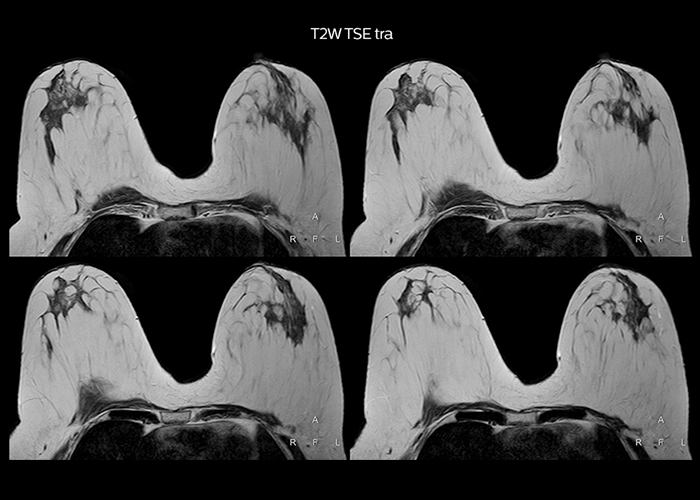

“Most important, Multiva satisfies our clinical imaging needs very well,” says Mr. Tuna. “Many features of Multiva have become similar to the Ingenia system. Even in more complex imaging such as abdominal and cardiac, the image quality and performance of Multiva is better than we expected. General surgeons and physicians from our hospital’s internal medicine department prefer to refer to us because of this.”

“To avoid coil changes we plan examinations of similar anatomies back to back, such as head and spine. Multiva helps us here a lot because coils don’t need to be changed frequently. Moreover, thanks to parallel imaging technology and 16-channel HeadSpineTorso and 8-channel MSK coils we are able to achieve excellent image quality. In this way Multiva helped us to increase both image quality and productivity.”